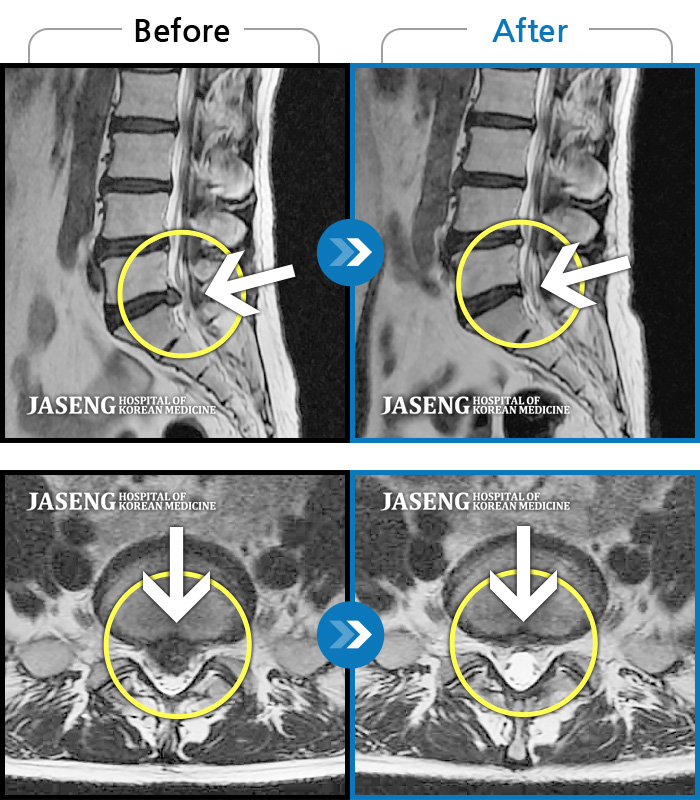

허리디스크

안산 · 김민수 원장

어떤 자세에도 통증이 지속되었다.

촬영시기

2018.10.25 ~ 2024.06.19

2024.07.31